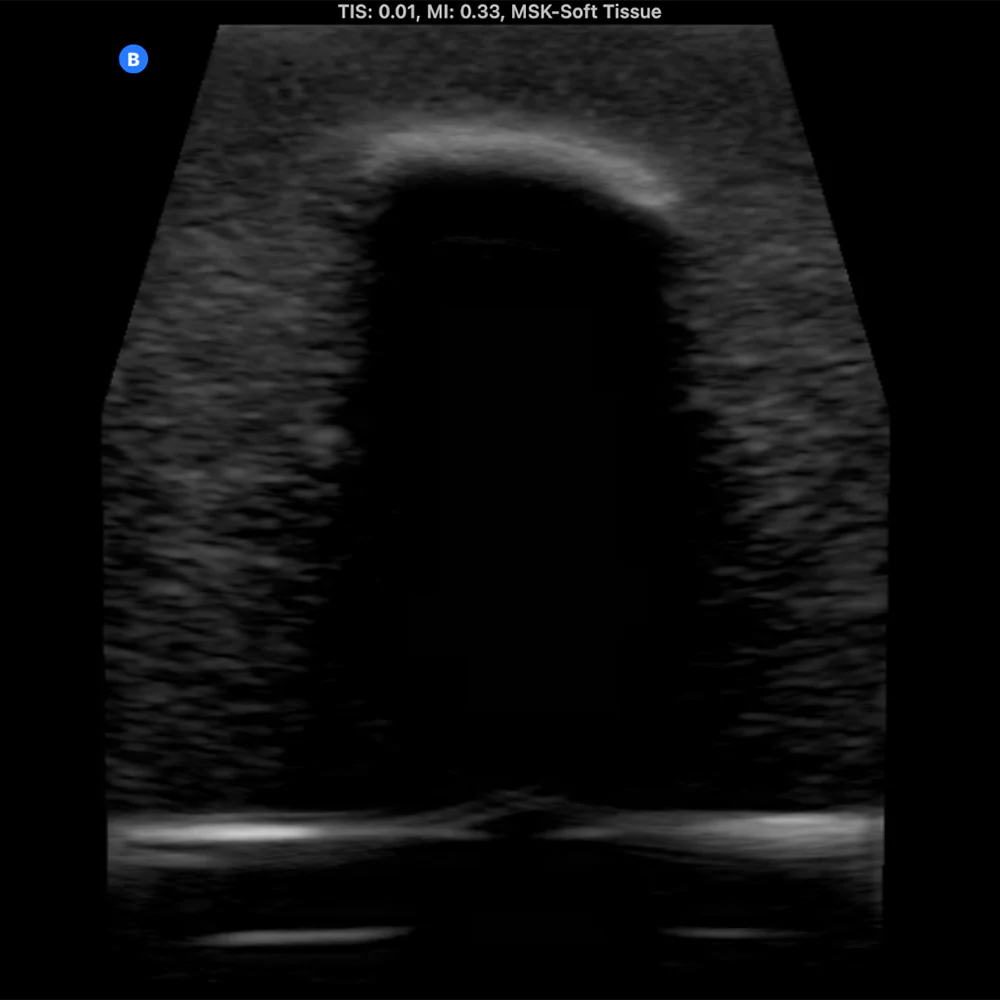

The Bone Fracture Ultrasound Phantom is an excellent training aid for developing the skills needed to identify bone fractures within soft tissue.

- Produces outstanding ultrasound image quality.